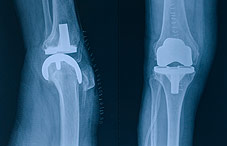

In a study published online in the Journal of Bone and Joint Surgery (Vol. 91, No. 12), researchers followed 57 patients scheduled to undergo knee surgery. Several days before surgery, patients gave blood samples to establish a baseline count of their lymphocytes, monocytes and neutrophils. On the morning of surgery, the researchers took another sample before patients were anesthetized, looking to see if patients’ anxiety about the surgery would increase the number of those immune cells. A halfhour after surgery, patients gave another blood sample. Based on their previous work, the researchers reasoned that at this later time during the short-term stress induced by surgery, many blood-borne immune cells would exit the circulation and enter tissues at the site of surgery, where they would begin the healing process.

The researchers found that patients whose immune systems responded to the stress of surgery by mobilizing large numbers of pathogen-fighting cells recovered more quickly and completely than patients whose immune cell count before surgery was unresponsive during the short-term stress. They also found that women were less likely than men to mount an adaptive stress response, leading to lower overall knee recovery. Dhabhar is now investigating whether the activation of “fight-or-flight” stress responses might enhance immune system protection in other contexts, such as after receiving a vaccination or during cancer treatment and recovery.